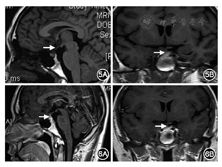

诊疗经过和预后:根据临床表现、实验室检查、影像学检查以及外院诊疗经过,弥凝治疗有效,功能诊断考虑中枢性尿崩症,垂体前叶各轴功能均正常。外院肋骨手术标本病理会诊:S-100(+),CD1α(+),langerin(+),CD68(-),LCA(-),Ki-67(+)(约30%),符合朗格汉斯组织细胞增生症(LCH)(图4)。病因诊断考虑为多系统LCH(累及垂体和肋骨)。治疗:继续弥凝片0.1 mg/次,2次/d控制尿量;原发病由血液科制定化疗方案。2014年8月11日起予以LCH-Ⅲ方案化疗1次[长春地辛4 mg(第1、8天)+地塞米松10 mg,1次/d(第1~8天)];2014年9月3日至10月17日给予长春地辛4 mg+醋酸泼尼松50 mg,1次/周,共5次;2014年10月29日至12月8日给予长春地辛4 mg(第1天)+醋酸泼尼松25 mg/次,2次/d(第1~3天),1次/周,共5次。患者减少并停用弥凝片,监测尿量维持2 000~3 000 ml/d。复查全身扁骨及长骨摄片未见明显异常,双侧颈部、锁骨上、腋下、腹股沟未见明显异常淋巴结肿大。垂体MRI平扫:垂体柄下方小结节,较前相仿,视交叉清晰(图5)。2014年12月11日至2015年9月25日继续给予长春地辛(第1天)+醋酸泼尼松25 mg/次,2次/d(第1~5天),每3周1次,共12次。治疗期间监测血糖、血脂、血压,未见异常,但体重增加15 kg。于2015年9月25日再次评估全身病情并未有复发情况。2016年1月行全身评估,三大常规、电解质、肝肾功能均在正常范围;垂体-甲状腺轴、肾上腺皮质轴、性腺轴评估均在正常范围;尿渗透压:557 mOsm/kg·H2O,尿量1 900 ml/d,腹部B超未见异常,全身扁骨及长骨X线片未见明显异常;查垂体MRI增强提示垂体柄结节状强化,病灶较前略有缩小(图6)。

LCH患者治疗方案的制定与随访也是临床一大挑战。由于LCH可累及全身多系统多病灶,在制定治疗方案前需对患者进行全身病情的评估。2013年关于青少年和成人LCH共识[5,6]推荐所有患者治疗前需要完成血常规、血生化(肝肾功能、电解质)、红细胞沉降率、C反应蛋白、凝血功能、腹部B超(肝、脾和淋巴结)、甲状腺B超及甲状腺功能、胸部X线片、全身骨X线片等常规检查,结合患者临床表现选择性行头颅或鞍区MRI检查,病变部位的活检等,PET-CT可替代B超、CT/MRI,更能发现病灶所在。进一步检查方案根据患者症状及基础评估结果而定[5]。本病例在肋骨病灶病理确诊LCH后,入院后查血、尿常规及电解质、肝肾功能正常、尿渗透压偏低,垂体-甲状腺轴、肾上腺皮质轴、性腺轴评估均在正常范围;肿瘤标志物在正常范围;腹部B超未及肝脾和腹腔淋巴结肿大,浅表淋巴结B超检查发现双侧腋下少量肿大淋巴结,骨穿检查未见造血系统累及;胸片未见异常;全身扁骨及长骨X线片未见异常。鞍区MRI增强:垂体柄下方结节状增粗;PET/CT示左侧第5肋骨病变治疗后,垂体柄稍饱满,余PET显像未见FDG代谢异常增高灶。结合烦渴、多尿、胸痛症状,考虑患者目前LCH累及骨骼和垂体柄。LCH的治疗依据其累及器官/系统的部位及多少[6,7]。2013年关于成人LCH诊治的欧洲共识[6]建议LCH累及单个系统时,主要是针对局部病灶的治疗,有两个以上系统累及或者一个系统多部位、危险器官(骨髓、肝、脾或中枢)累及者需行系统治疗;对于症状明显的多系统累及患者,建议阿糖胞苷(cytarabine)100 mg/m2(第1~5天),每4周1次静脉滴注,或者依托泊苷(etoposide)100 mg/m2(第1~5天),每4周1次静脉滴注,长春地辛和泼尼松龙的治疗类似儿科中的使用。2~3个疗程后需要评估患者病情,如果病情有进展或活动,需要进行类似治疗前的全面评估。本病例中,患者19岁,病灶累及骨骼及垂体柄两个系统,根据目前LCH治疗共识[6,7]给予长春地辛联合醋酸泼尼松的治疗方案。治疗后随访患者尿崩症状有明显改善,包括骨骼系统在内全身各系统检查并未发现新发病灶,最后一次随访中其垂体MRI提示垂体柄区域病灶明显缩小,尿崩逆转,提示治疗效果好。该患者垂体病变仅累及垂体柄,且病灶较小,临床上仅表现为尿崩,治疗前后无其他下丘脑功能障碍如贪吃、嗜睡等,但体重增加15 kg,考虑为治疗方案中糖皮质激素的不良反应。如LCH累及下丘脑者应注意下丘脑功能障碍伴随的摄食障碍和代谢异常,在选择治疗方案时尽可能避免糖皮质激素。